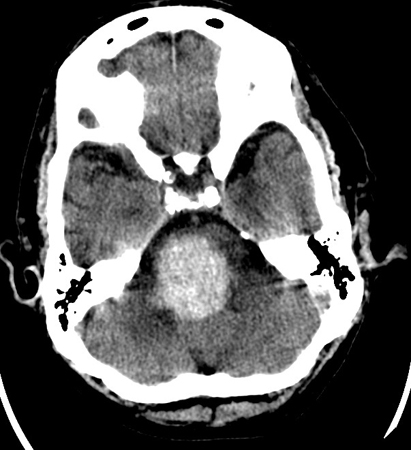

Hemorragia hipertensiva em uma ponte que se rompeu no quarto ventrículo e estendeu-se para o mesencéfalo

Do acervo pessoal de G. Bryan Young, MD; usado com permissão